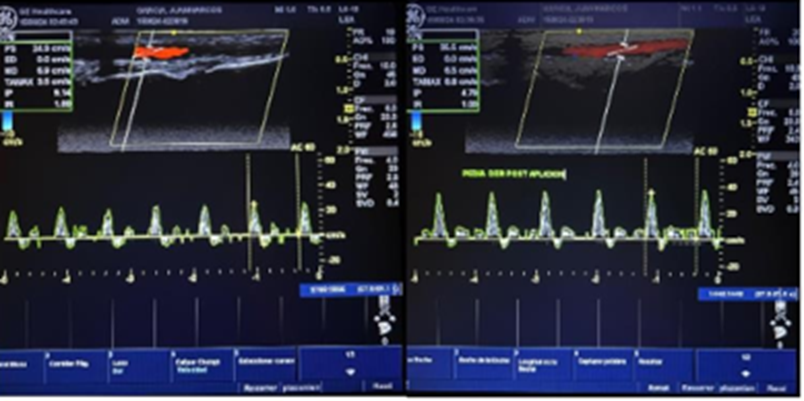

The patients underwent an arterial and venous Echo Doppler before and after the first application to rule out arterial involvement and to observe any changes in stroke flow at the microcirculatory level. We evaluated

onthe other hand, the patientmanifests clear improvement in the appearance of nutrition, turgor, and elasticity of the ulcer in the skin around the ulcer. It should be noted that studies were carried out with high-resolution Doppler echo and general equipment electric versant balance, in which an increase in peak arterial flow was observed in images.

Peak systolic flow increases artery pedia by 3% immediately after the first application of the CO2 transdermal gel. “Peak systolic velocity (PSV) is an index measured in spectral Doppler ultrasound. On a Doppler waveform, the peak systolic velocity corresponds to each tall “peak” in the spectrum window.”

In all cases, a Venous and Arterial echo Doppler were performed before and after the first application. The Venous Doppler showed different gradations or manifestations of chronic venous insufficiency, such as edema, reflux, and chronic DVT.

The Arterial Doppler done after the immediate application of the gel showed an increase in the peak stroke flow. The rise in blood flow consequently increased the oxygenation of the compromised tissue perfusion.

Notably, there were enhancements in the post-immediate arterial Doppler after the use of the combination of gels that produce CO2. There was an average increase in the systolic peak between 1.5 to 3%.